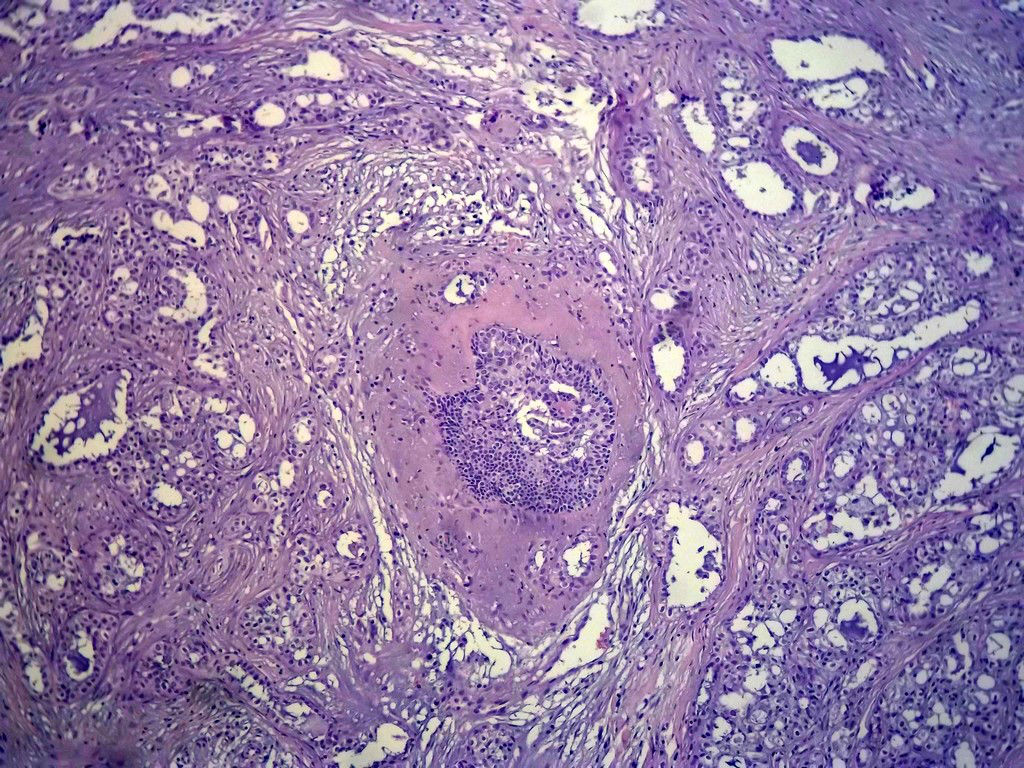

今天的一例术中冰冻。女,49岁,乳腺肿块。人气不旺,换个标题

腺病?癌?其他?(12楼常规,24楼免疫组化及会诊结果)图1

标签:浸润性导管癌 分泌癌 硬化性腺病

乳腺分泌型癌

1. Most likely no invasive cancer

2 Sclerosing adenosis

3 Ductal epithelial hyperplasia

4. Bundles d Smooth muscle?

导管是乎可见双层上皮,部分上皮增生并有一定异型,考虑硬化性腺病,待石蜡。

导管可见双层上皮,部分上皮增生并有一定异型,考虑硬化性腺病

腺体与腺体之间的对比差异太大,不放心,不除外是癌,如果是我的病例,再次取材冰冻

占楼传常规1-11为冰对。